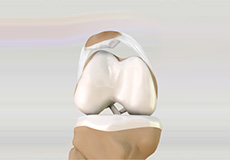

The joint surface is covered by a smooth articular surface that allows pain-free movement in the joint. Arthritis is a general term covering numerous conditions where the joint surface or cartilage wears out.

Osteoarthritis also called degenerative joint disease, is the most common form of arthritis. It occurs most often in older people. This disease affects the tissue covering the ends of bones in a joint (cartilage).